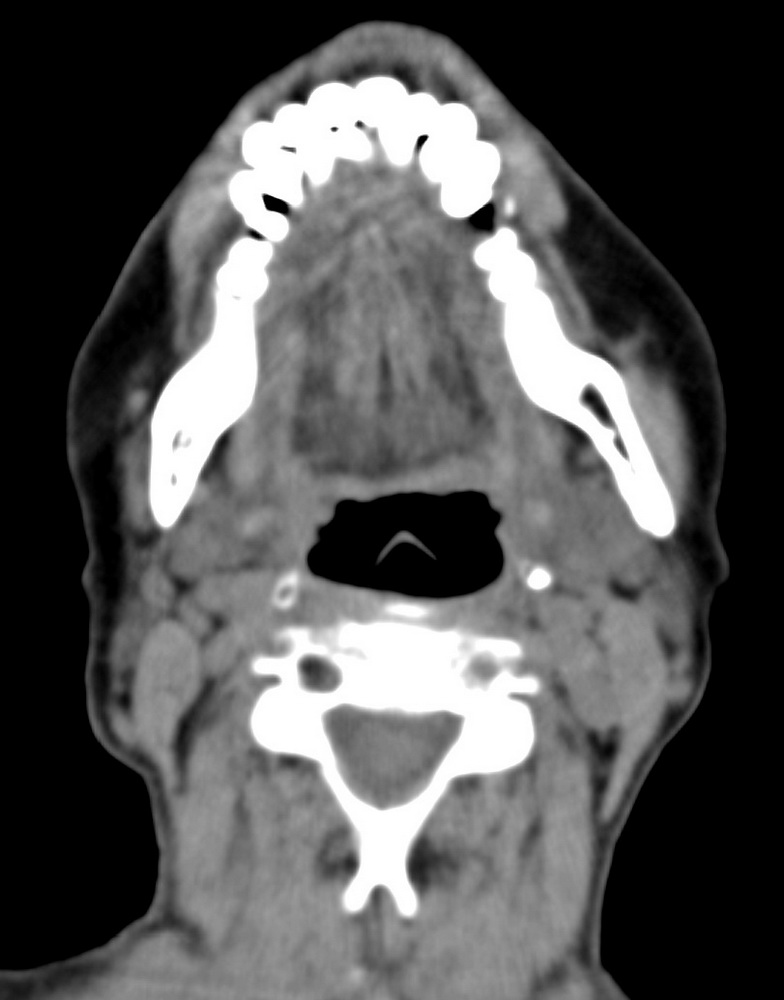

女,68岁。发现上唇无痛性肿块2年多,查体局部皮肤隆起,其余未见异常。

病灶ct值约42hu。

病理结果:唾液腺混合瘤。